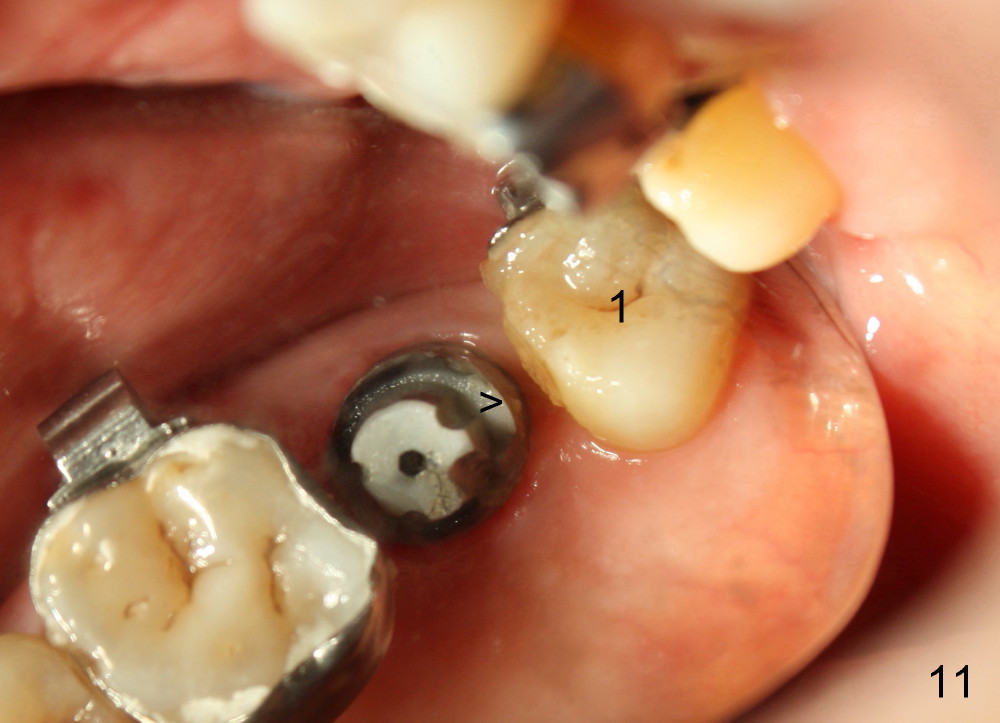

A 48-year-old lady is a dental phobic and has generalized chronic periodontitis. Bone loss around the tooth #2 has been severe for the last 5 years (Fig.1,2 *). Finally she agrees to have #2 (symptomatic) extracted and immediate implant placed (Fig.3 I). A 7x17 mm implant has to be used to achieve primary stability. The remaining buccal and lingual gaps are filled with allograft and membrane (Fig.4 *). Fig.5 shows that there is a space between the tooth #1 (asymptomatic) and the immediate implant (I). The wound/socket is protected by applying perio dressing around an abutment (Fig.6 A). Postop the patient is pain free; the perio dressing dislodges by itself. She returns 3.5 months later for restoration; but the tooth #1 has shifted mesially (Fig.6 arrow). The patient is not so willing to have #1 removed. Bands and bracket are placed in the neighboring teeth including a provisional crown to move the shifted tooth (with mobility) distally (Fig.7,9). The 2nd reason for #1 shifting is abnormal occlsual scheme on the right posterior region (Fig.8); mobility of #1 is the 1st one. The 3rd one is probably bruxism. In 5-6 weeks, the tooth #1 has moved to a desirable position (Fig.10, as compared to Fig.3,5). There is enough space for restoration (Fig.11,12).